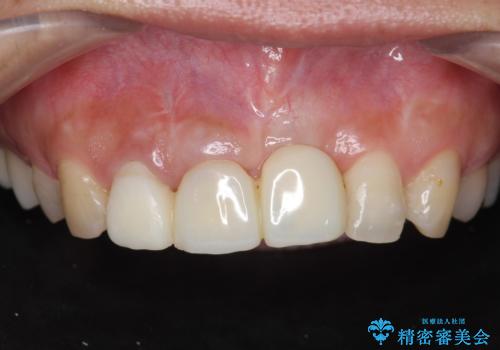

不良インプラントの除去・骨造成・歯肉移植・前歯審美セラミックブリッジ製作

不良インプラントを除去し最終的にブリッジによる補綴で審美性の改善を行うこと、その準備として骨の造成・歯肉の移植による歯の欠損部顎堤のボリュームを維持・増大を計画します。

より審美的な改善を強く求められたため、インプラントを除去し可及的に欠損部顎堤を増大したのちブリッジによる審美改善を行いました。